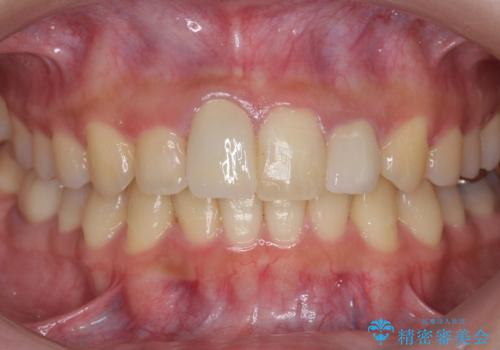

[ マウスピース矯正] 前歯のがたつき 出っ歯に見える歯をきれいに

![[ マウスピース矯正] 前歯のがたつき 出っ歯に見える歯をきれいに の症例 治療前](https://seimitsushinbi.jp/wp/wp-content/uploads/2025/04/IMG_0123-500x350.jpg?v=1744960747)